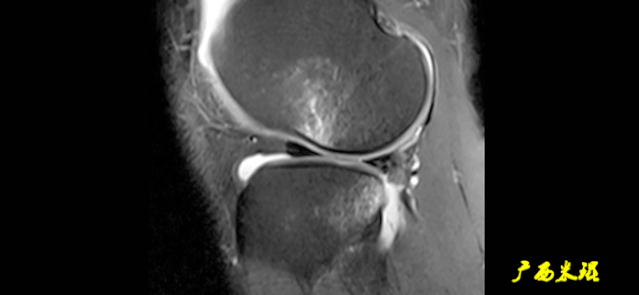

6)假瘤:

韧带损伤后断端较整齐,残端组织增生并被滑膜包裹呈“瘤状”,如果突出于前方为“独眼征”。

多见于韧带股骨附着部撕裂及部分撕裂。